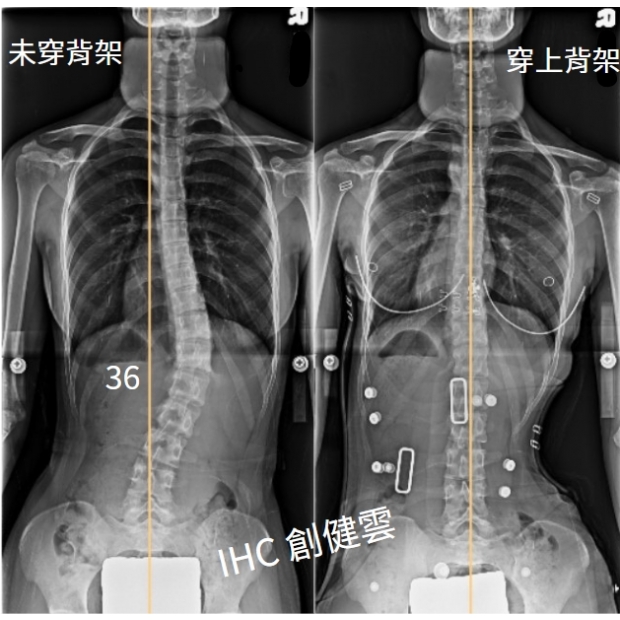

17歲脊椎側彎女生,腰彎36度